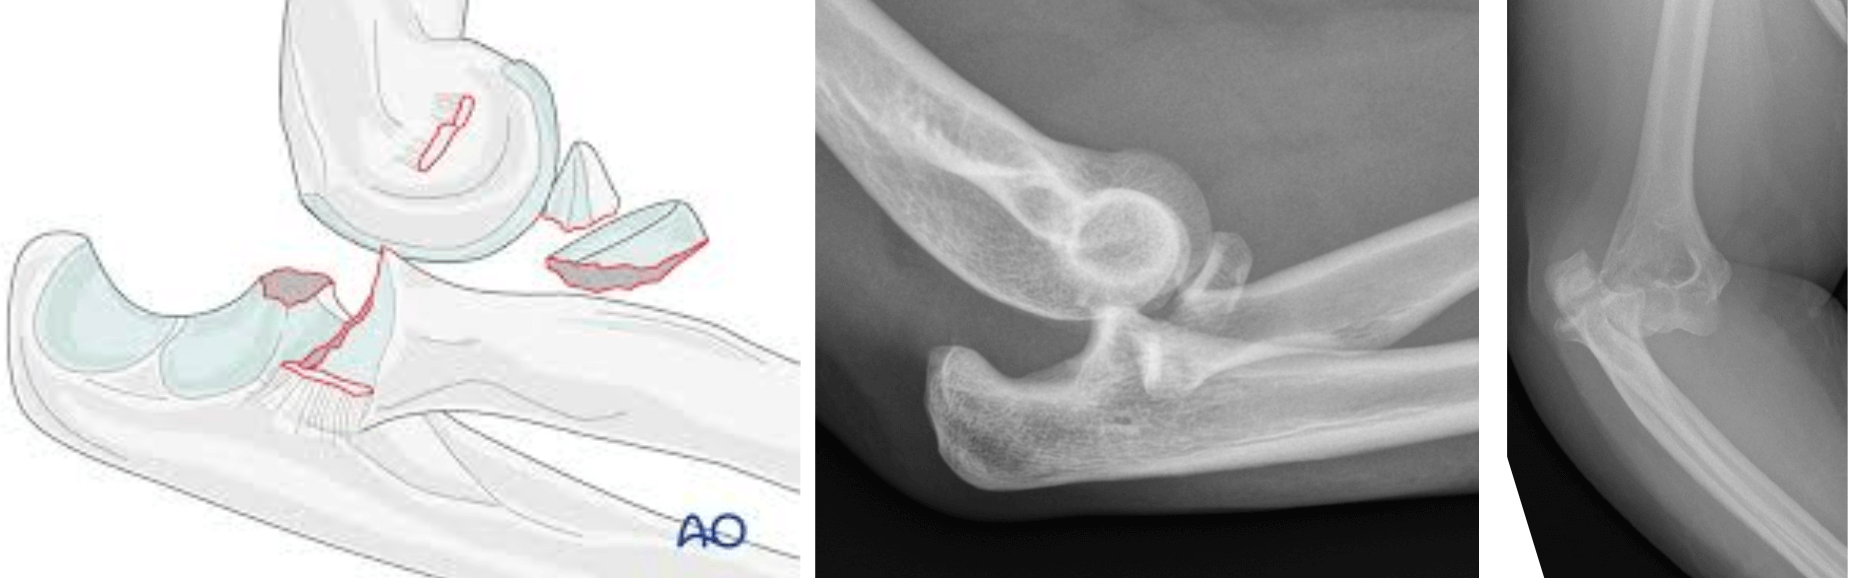

Fractura de Gartland desplazada: Las fracturas de Gartland son fracturas supracondíleas de húmero distal que ocurren en pacientes pediátricos (niños), estas pueden ser tratadas con un yeso o incluso necesitar cirugía para reducir y fijarla + un yeso.

ANTES: Luxofractura codo derecho: - en emergencia se reduce, se hacen diagnósticos y planificamos cirugía.

DESPUÉS: Luxofractura de codo post cirugía y en rehabilitación, con adecuados movimientos en flexoextensión y pronosupinación.